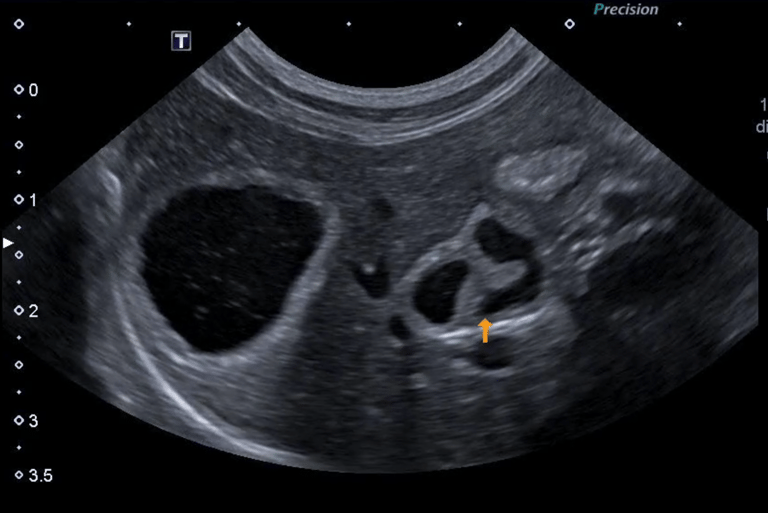

4 - Est ce que l’image obtenue vous semble correcte ?

A - Oui

B - Non

C - Je ne sais pas

5- Si non, expliquez quel réglage serait intéressant de modifier pour obtenir une image échographique correcte

A - J'ai coché oui à la réponse précédente

B - Diminuer la profondeur

C - Augmenter la profondeur

D - Augmenter le gain étagé en profondeur

E - Diminuer le gain étagé en profondeur

6- De quel organe s’agit-il ? Précisez G ou D et le plan de coupe réalisé

A - Le Rein Gauche en coupe transversale

B - Le Rein Droit en coupe transversale

C - Le Rein Gauche en coupe longitudinale

D - Le Rein Droit en coupe longitudinale

E - La Surrénale droite en coupe transversale

7 - En sachant que l'autre rein présente le même aspect échographique, et qu'ils mesurent tous les deux 3,5 cm de long, vous pouvez conclure :

A - Absence d'anomalie échographique visible

B - Nephromégalie bilatérale

C - Dilatation de la cavité pyélique

D - Signes échographiques en faveur d'une néphrite tubule-interstitielle

E - Signes échographiques en faveur d'une glomerulonephrite